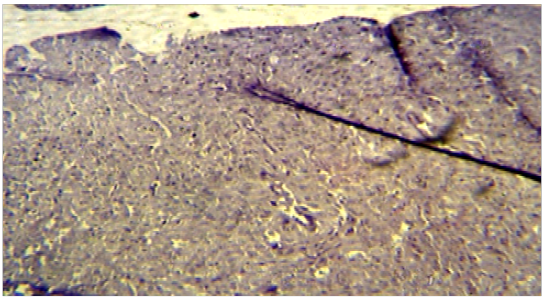

Histopathological section of G2 showed the endometrium of uterus and the presence of surface epithelium, lamina properia and increase number of endomaterial gland with dilation of blood vessels (H&E X 100).

Histopathological section of G3 showed increase in number of the endometrial glands that glandular epithelia are tall columnar with rounded basal nuclei and blood capillaries, and stromal cells, as compared with control group (H&E X 40).

Histological section in G1 showed normal uterine tissue (H&E X 100).